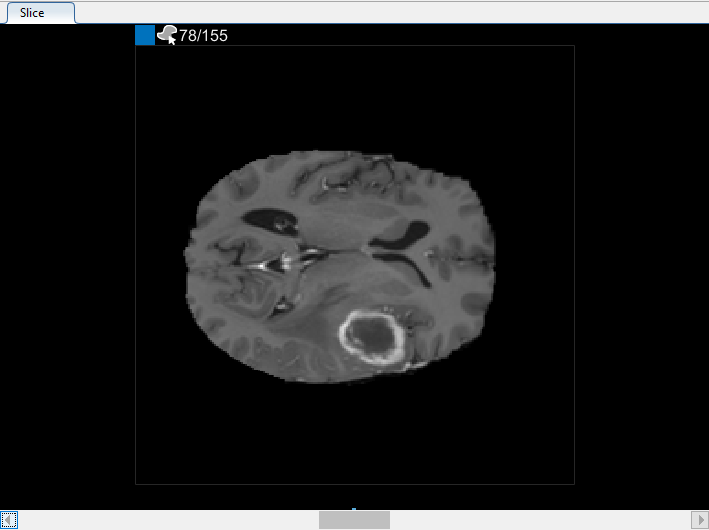

В 3-D панели Отображения можно вращать объем, чтобы исследовать данные с разных сторон, с помощью мыши. Можно также настроить отображение объема в 3-D вкладке Display в панели инструментов приложения. Например, если у вас есть метаданные, которые описывают относительный размер вокселей, можно задать его в Пространственной части Ссылки 3-D вкладки Display в панели инструментов приложения. Чтобы улучшить ваше представление данных, можно изменить цвет фона, используемый в 3-D отображении, изменить порог и непрозрачность отображения, и включать оси ориентации с отображением, как показано в рисунке ниже. С мозговыми данными MRI вы видите опухоль в височной доле, которую вы хотите сегментировать.

Можно также просмотреть каждый срез объема в панели Среза. Используйте ползунок в нижней части панели, чтобы переместиться от среза до среза. Вы видите опухоль на срезе 35 через срез 88. По умолчанию панель Среза отображает объем, ориентированный вдоль оси X-Y, но можно изменить это использование кнопки в разделе Orientation панели инструментов на вкладке Segmenter. Панель Среза также, где вы используете инструменты для рисования, чтобы задать маску.